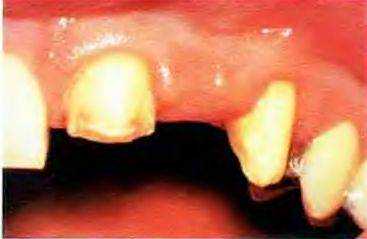

Рис. 13-6. В данном случае зуб был также препарирован только в одной плоскости. Для создания достаточного пространства для реставрации на вестибулярной поверхности резца и во избежание неудовлетворительного косметического результата, продемонстрированного на предыдущем слайде, было проведено чрезмерное препарирование. В результате этого произошло обнажение рогов пульпы, что потребовало эндодонтического лечения